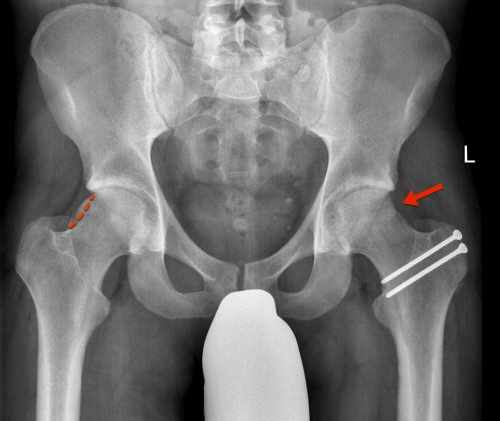

Der „Goldstandard“ in der Behandlung des femoroazetabulären Impingements stellt die chirurgische Hüftluxation dar. Nach dem Ausrenken des Hüftkopfs aus der Hüftgelenkspfanne ist eine optimale Sicht auf beide Gelenkpartner möglich, die eine sorgfältige Behandlung aller Aspekte eines femoroazetabulären Impingements erlaubt. Um den Hüftkopf aus der Hüftgelenkspfanne ausrenken zu können, ist in einem ersten Operationsschritt die Ablösung des grossen Rollhügels (Trochanter major) vom Oberschenkelknochen nötig (Trochanter-Flip-Osteotomie). Der abgelöste Trochanter major wird am Ende der Operation mit zwei Schrauben refixiert, um das Wiederanheilen zu ermöglichen.